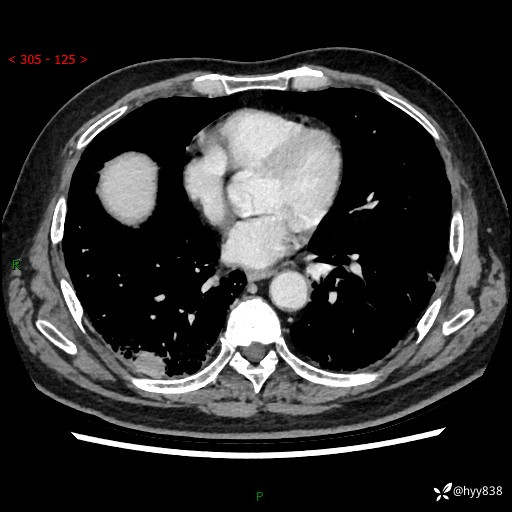

71岁/男,咳嗽伴气促半月。一年前肺手术史,又见两个结节,穿刺结果意外---结果公布~

【现病史】:患者半月前无明显诱因出现咳嗽、咳痰,为白色粘痰,无明显加重与缓解因素,伴气促,无发热,无大量脓痰,无胸痛、咯血,无哮鸣音,到我院就诊,胸部CT示右肺结节增大,并口服药物治疗无明显好转,具体用药不详,为求进一步治疗随来我院,经门诊以“孤立性肺结节”收入我科。 病程中患者精神、饮食可,睡眠不佳,大小便正常,体力下降,体重未见明显下降。

[既往史]:2022-06于当地第一人民医院确诊慢阻肺,现规律使用杰润(1次/日);2023-04-06于当地市第一人民医院行胸腔镜右肺上叶楔形切除术+右肺上叶切除术+淋巴结清扫术+胸膜黏连松解术,确诊为右肺鳞癌 pT2aN0M0 Ib期

【检查】:胸部CT平扫+增强